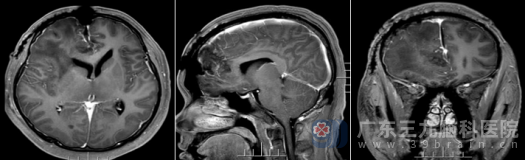

术后复查MR证实:原病变已完全切除。更令人欣慰的是,术后病理诊断为孤立性纤维性肿瘤(CNS WHO 1级)——这是一种预后较好的低级别肿瘤。

术后,陈某恢复顺利。出院时,他已神志清醒,右眼视力较术前明显好转,四肢活动自如。不仅摆脱了肿瘤的威胁,更保住了宝贵的视功能。